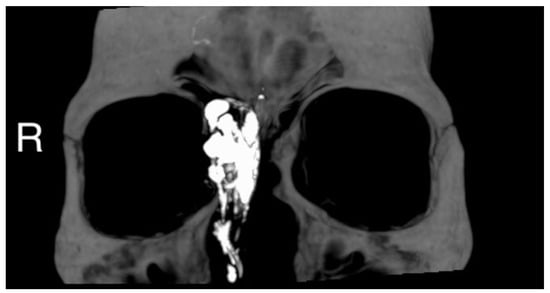

Figure 3.

Intraoperative view of the tumor through a trans-sinusal frontal approach.